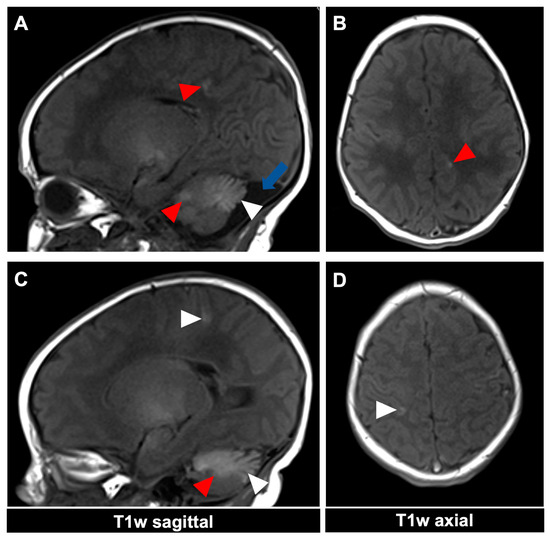

Figure 3.

MR imaging of an 11-day-old female patient with neurocutaneous melanosis (NCM) using an MRI-compatible incubator. (A–D) Imaging findings of leptomeningeal (white arrowhead) and intraparenchymal melanosis (red arrowhead) demonstrate a high T1 signal in sagittal and corresponding axial planes. The image examples illustrate that acquiring two different planes of T1-weighted sequences is advantageous, as it is sometimes difficult to distinguish between leptomeningeal and intraparenchymal manifestations. The patient also has an infratentorial arachnoid cyst ((A), blue arrow). T1w = T1-weighted.